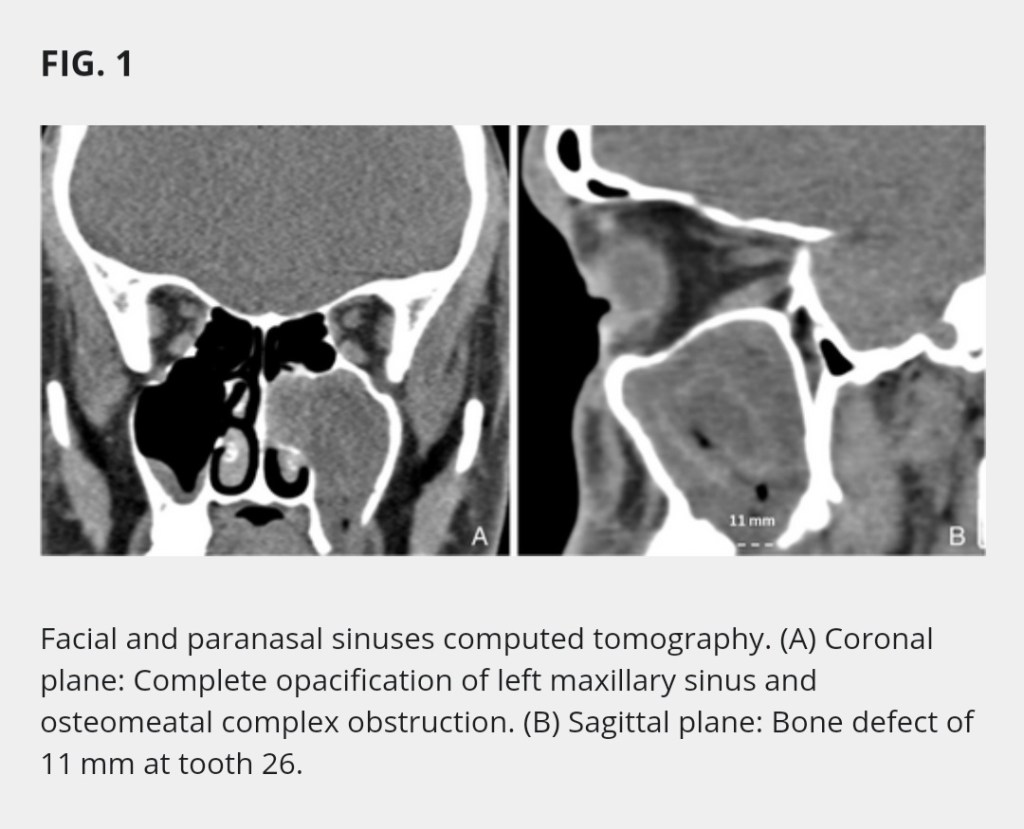

This case – a 30-year-old man visited the emergency department with a history of 4 months of purulent nasal discharge and facial pain in the context of upper left molar extraction that did not respond to long-term antibiotic treatment. Nasal endoscopy showed purulent discharge coming from the left middle meatus and a bulging uncinate process. Oral cavity inspection manifested granulation tissue with purulent discharge at the site of tooth 26. Facial and paranasal sinuses computed tomography (CT) was performed, it showed an 11 mm bone defect at the left maxillary floor concerning tooth 26 and a complete opacification of the maxillary sinus with osteomeatal complex obstruction